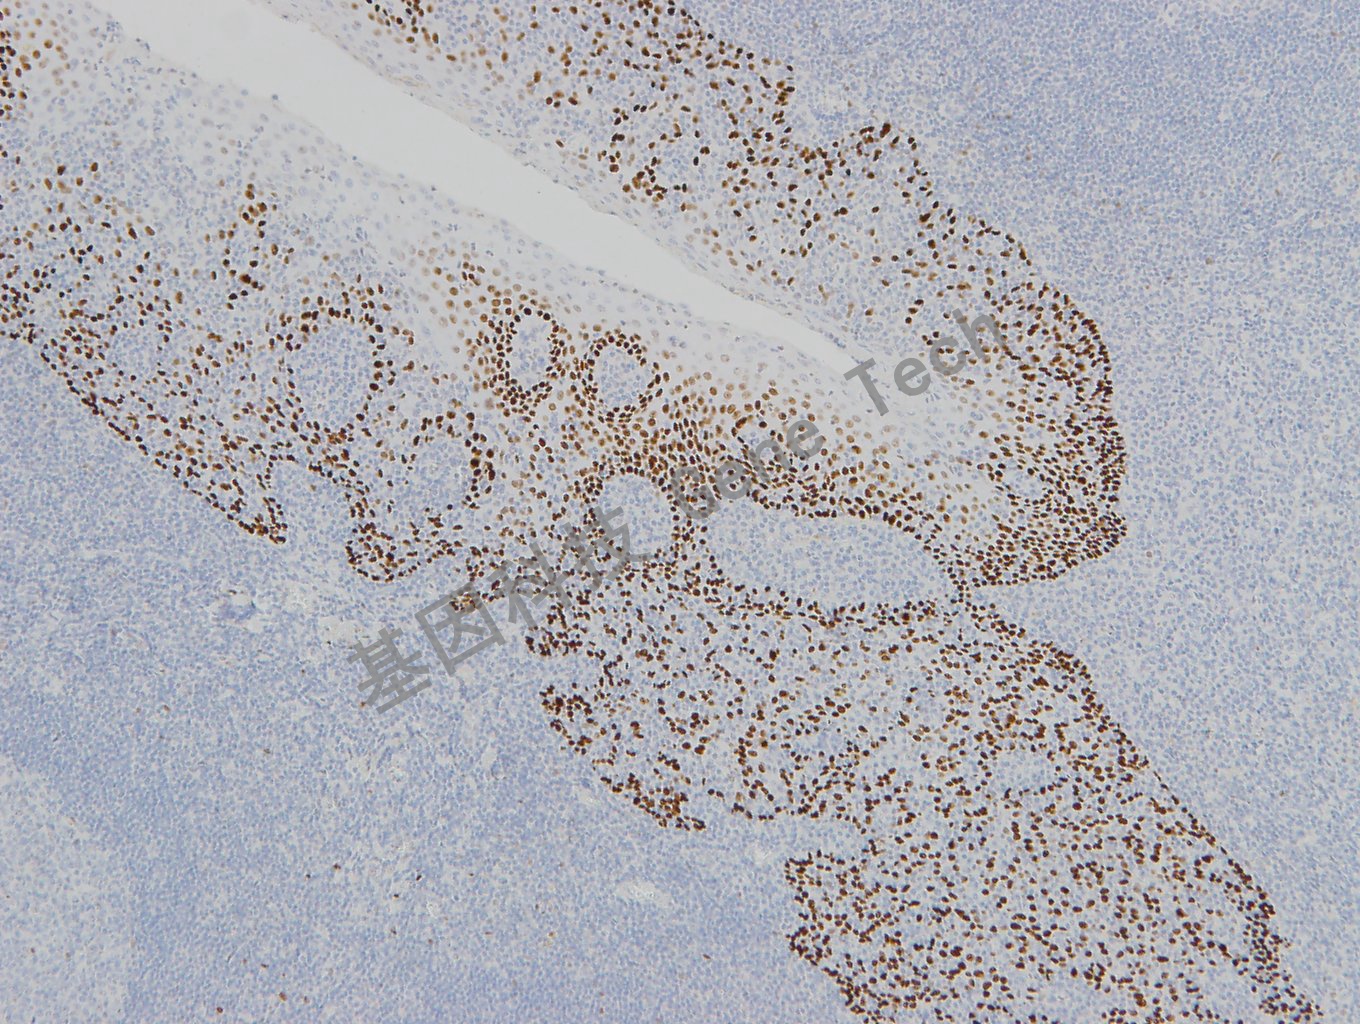

前列腺石蜡切片,用 p63(GT2331)染色,细胞核阳性,DAB 显色。

前列腺石蜡切片,用 p63(GT2331)染色,细胞核阳性,DAB显色。